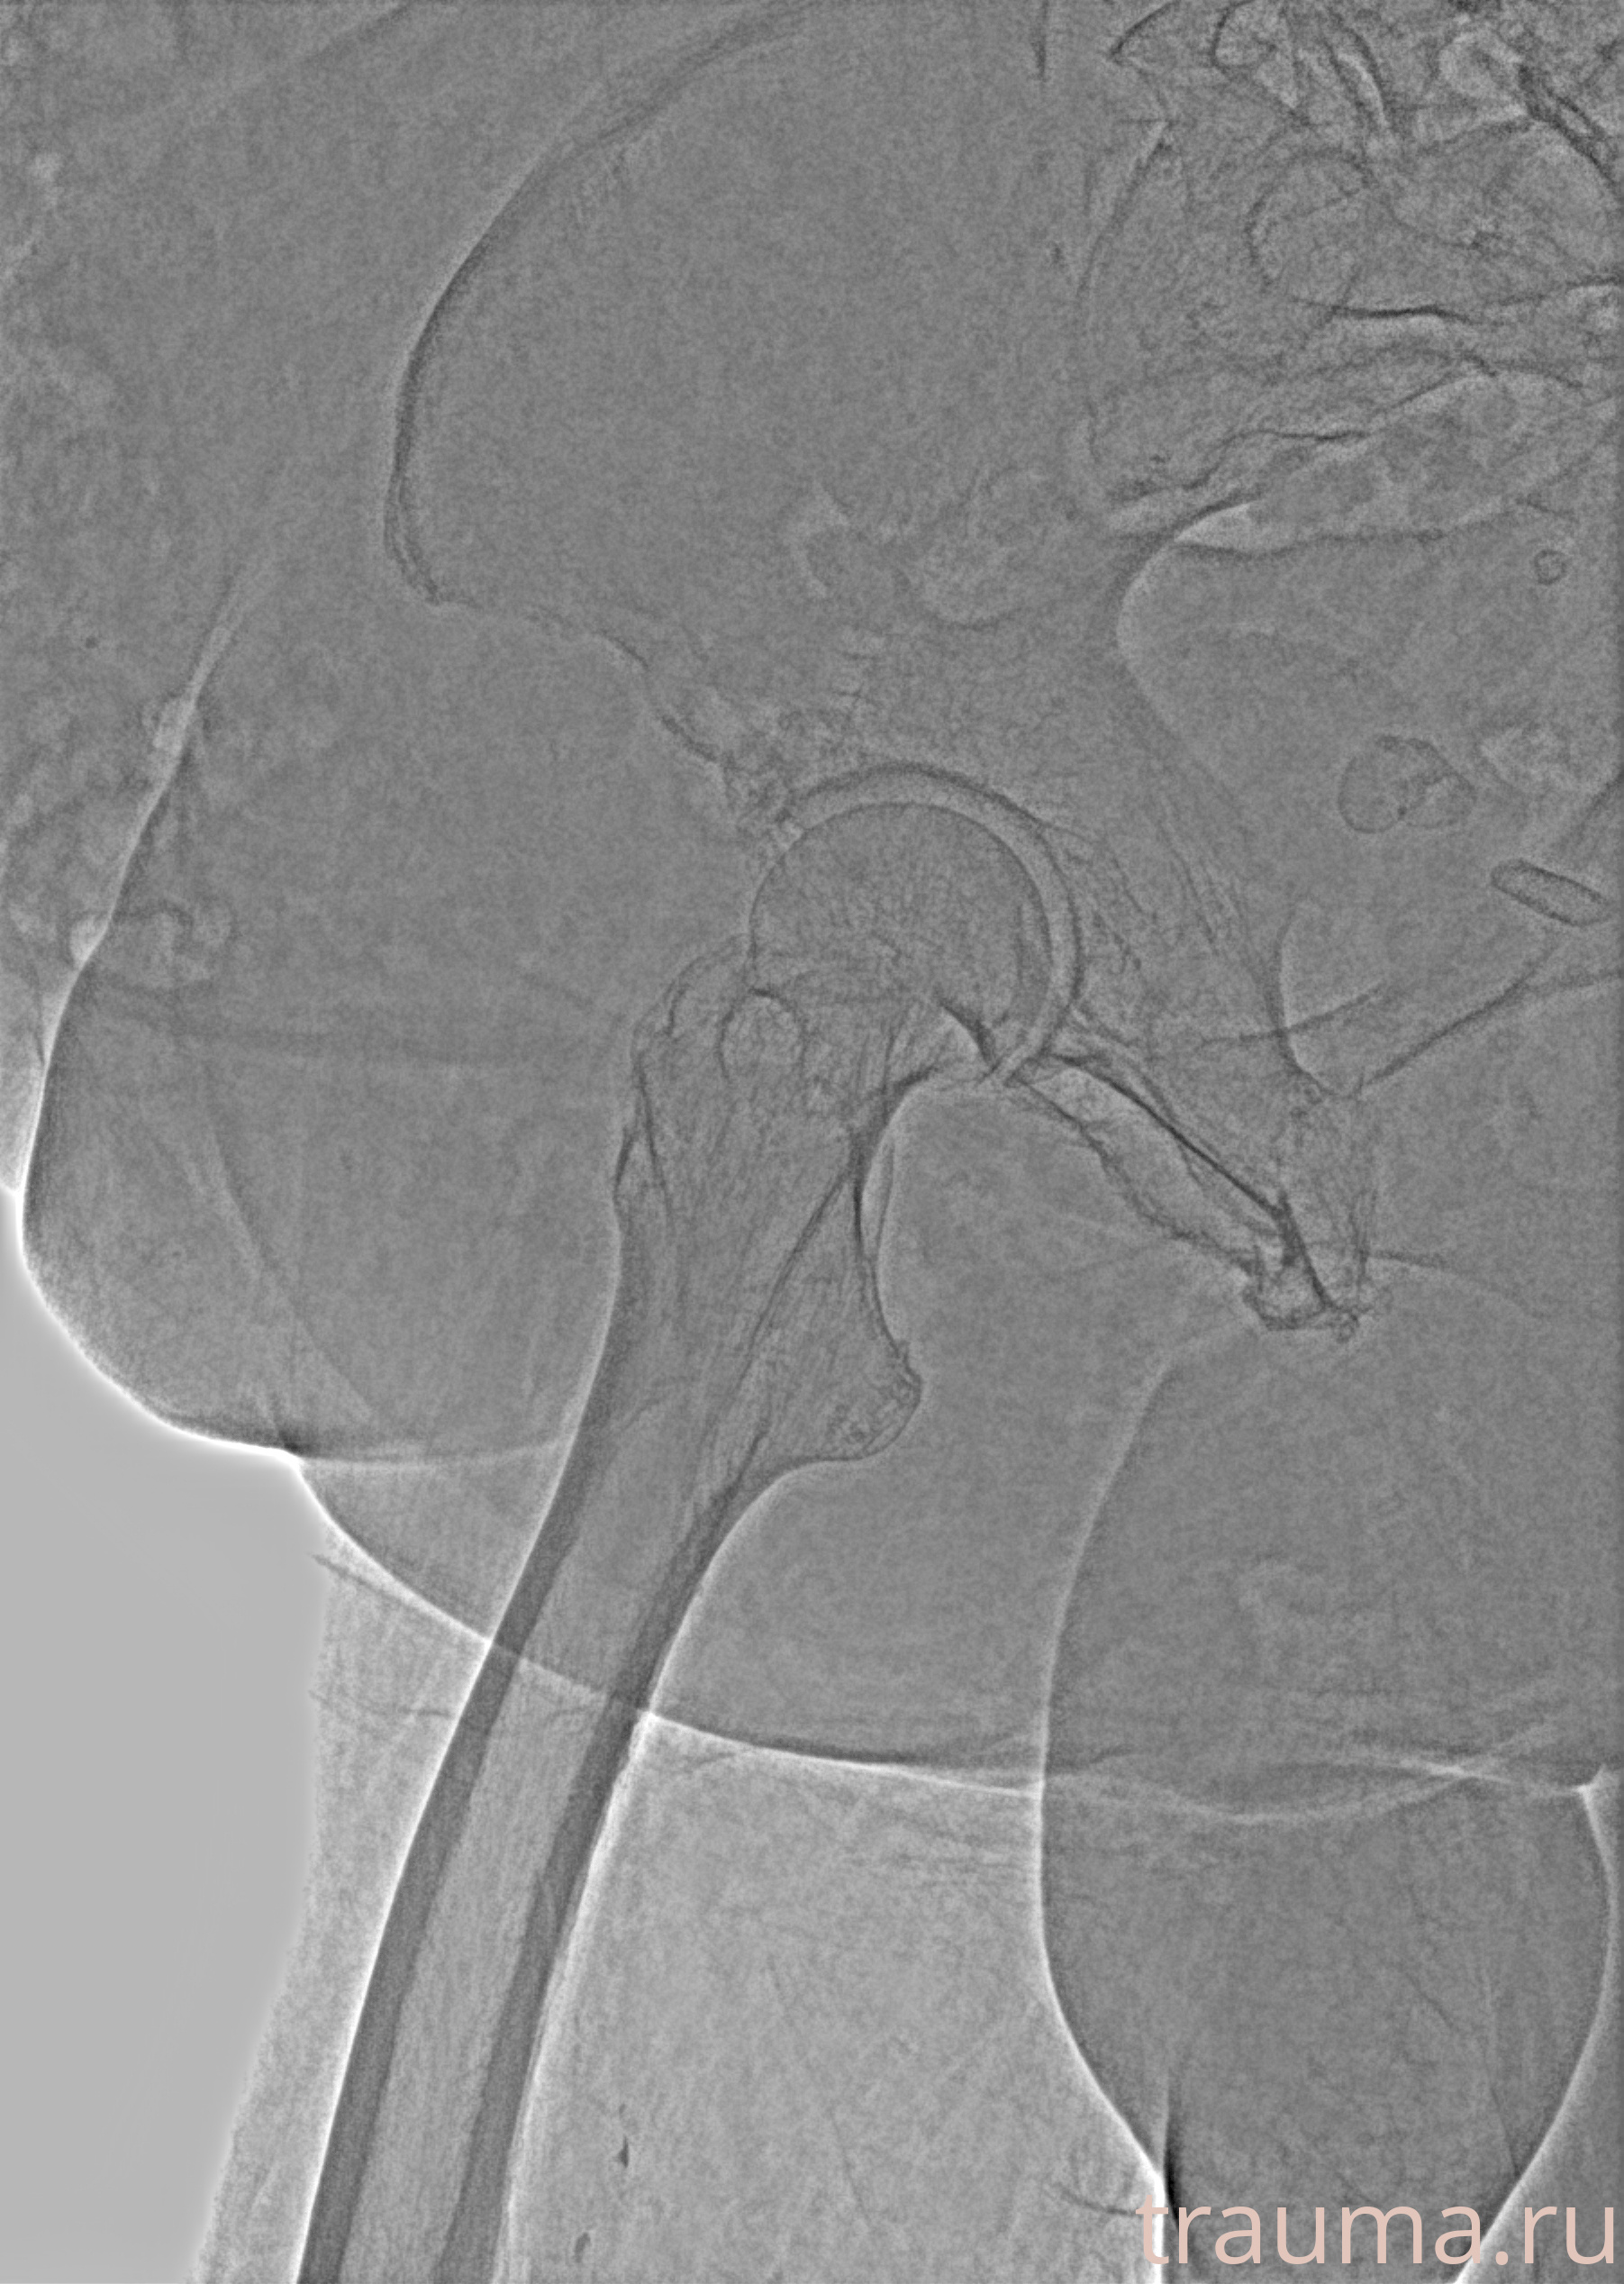

Рентгенограммы

Рентген на дому: по вашему адресу приезжает врач-рентгенолог, травматолог-ортопед с мобильным рентгеновским аппаратом, проводит диагностику травмы или заболевания, делает необходимые рентгенограммы, дает рекомендации по дальнейшему лечению. Получить качественные снимки в домашних условиях возможно благодаря уникальной методике, разработанной МосРентген Центром для института  Склифосовского